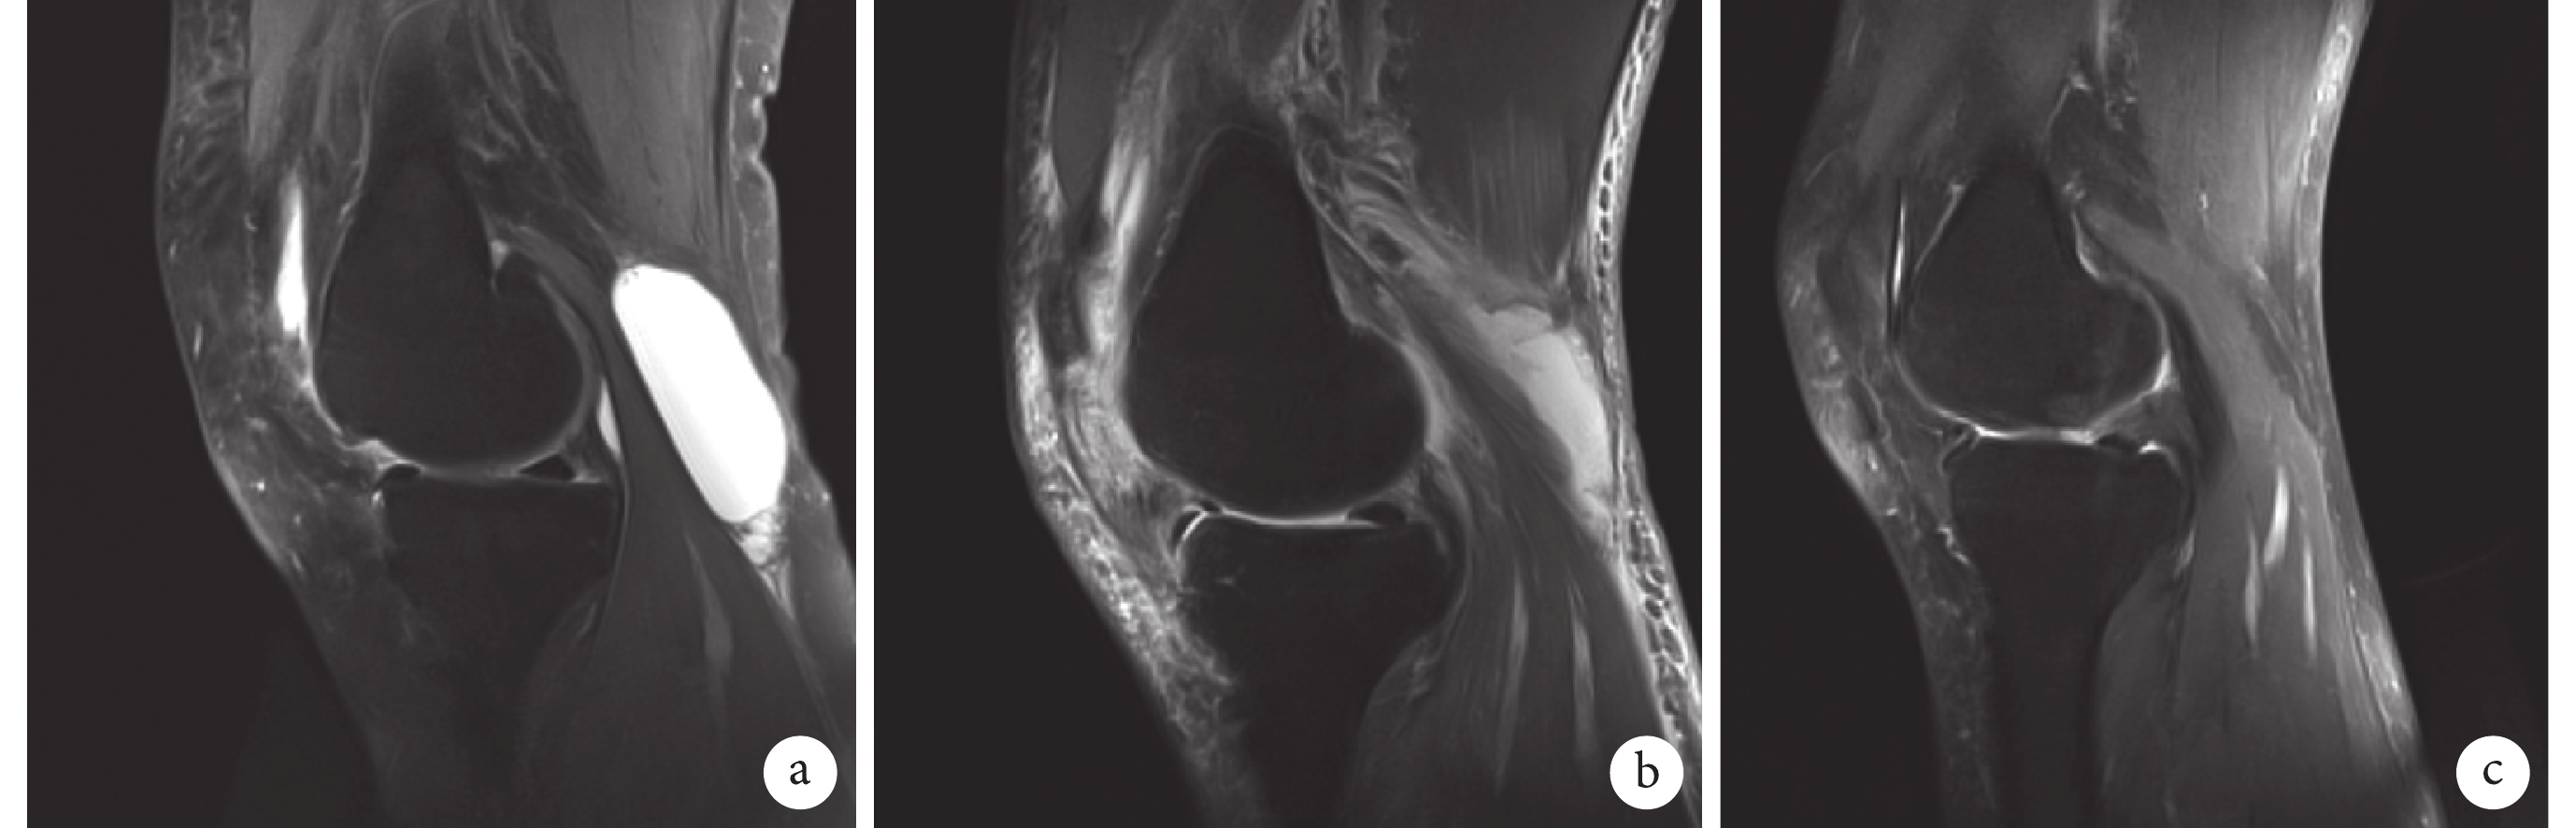

術后 1 年 Rauschning 和 Lindgren 分級[16],試驗組 0 級 16 例、1 級 6 例、2 級 4 例,對照組 0 級 17 例、1 級 4 例、2 級 6 例,兩組比較差異無統計學意義(Z=–1.872,P=0.078)。MRI 檢查示,試驗組 9 例(34.62%)仍有殘余囊腫,最大直徑 0.5~1.7 cm,平均 1.3 cm;對照組 13 例(48.15%)仍有殘余囊腫,最大直徑 0.4~1.9 cm,平均 1.7 cm;兩組其余患者囊腫均消失,隨訪期間無復發。兩組囊腫殘留率比較,差異無統計學意義(χ2=2.293,P=0.852)。見圖 2、3。

a. 術前;b. 術后 1 周;c. 術后 1 年

Figure3. MRI of a 55-year-old female patient with left popliteal cyst in the control groupa. Before operation; b. At 1 week after operation; c. At 1 year after operation

Figure2. MRI of a 48-year-old male patient with right popliteal cyst in the trial groupa. Before operation; b. At 1 week after operation; c. At 1 year after operation